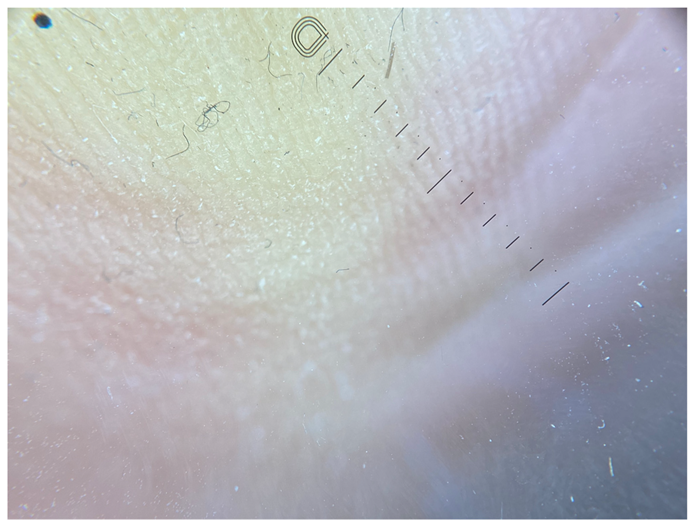

| Grade III | Foto Finder dermatoscopy, cross-polarization |

![]() | |

| DL-5 dermatoscopy, cross-polarization | |

| DL-5 dermatoscopy, parallel polarization | |